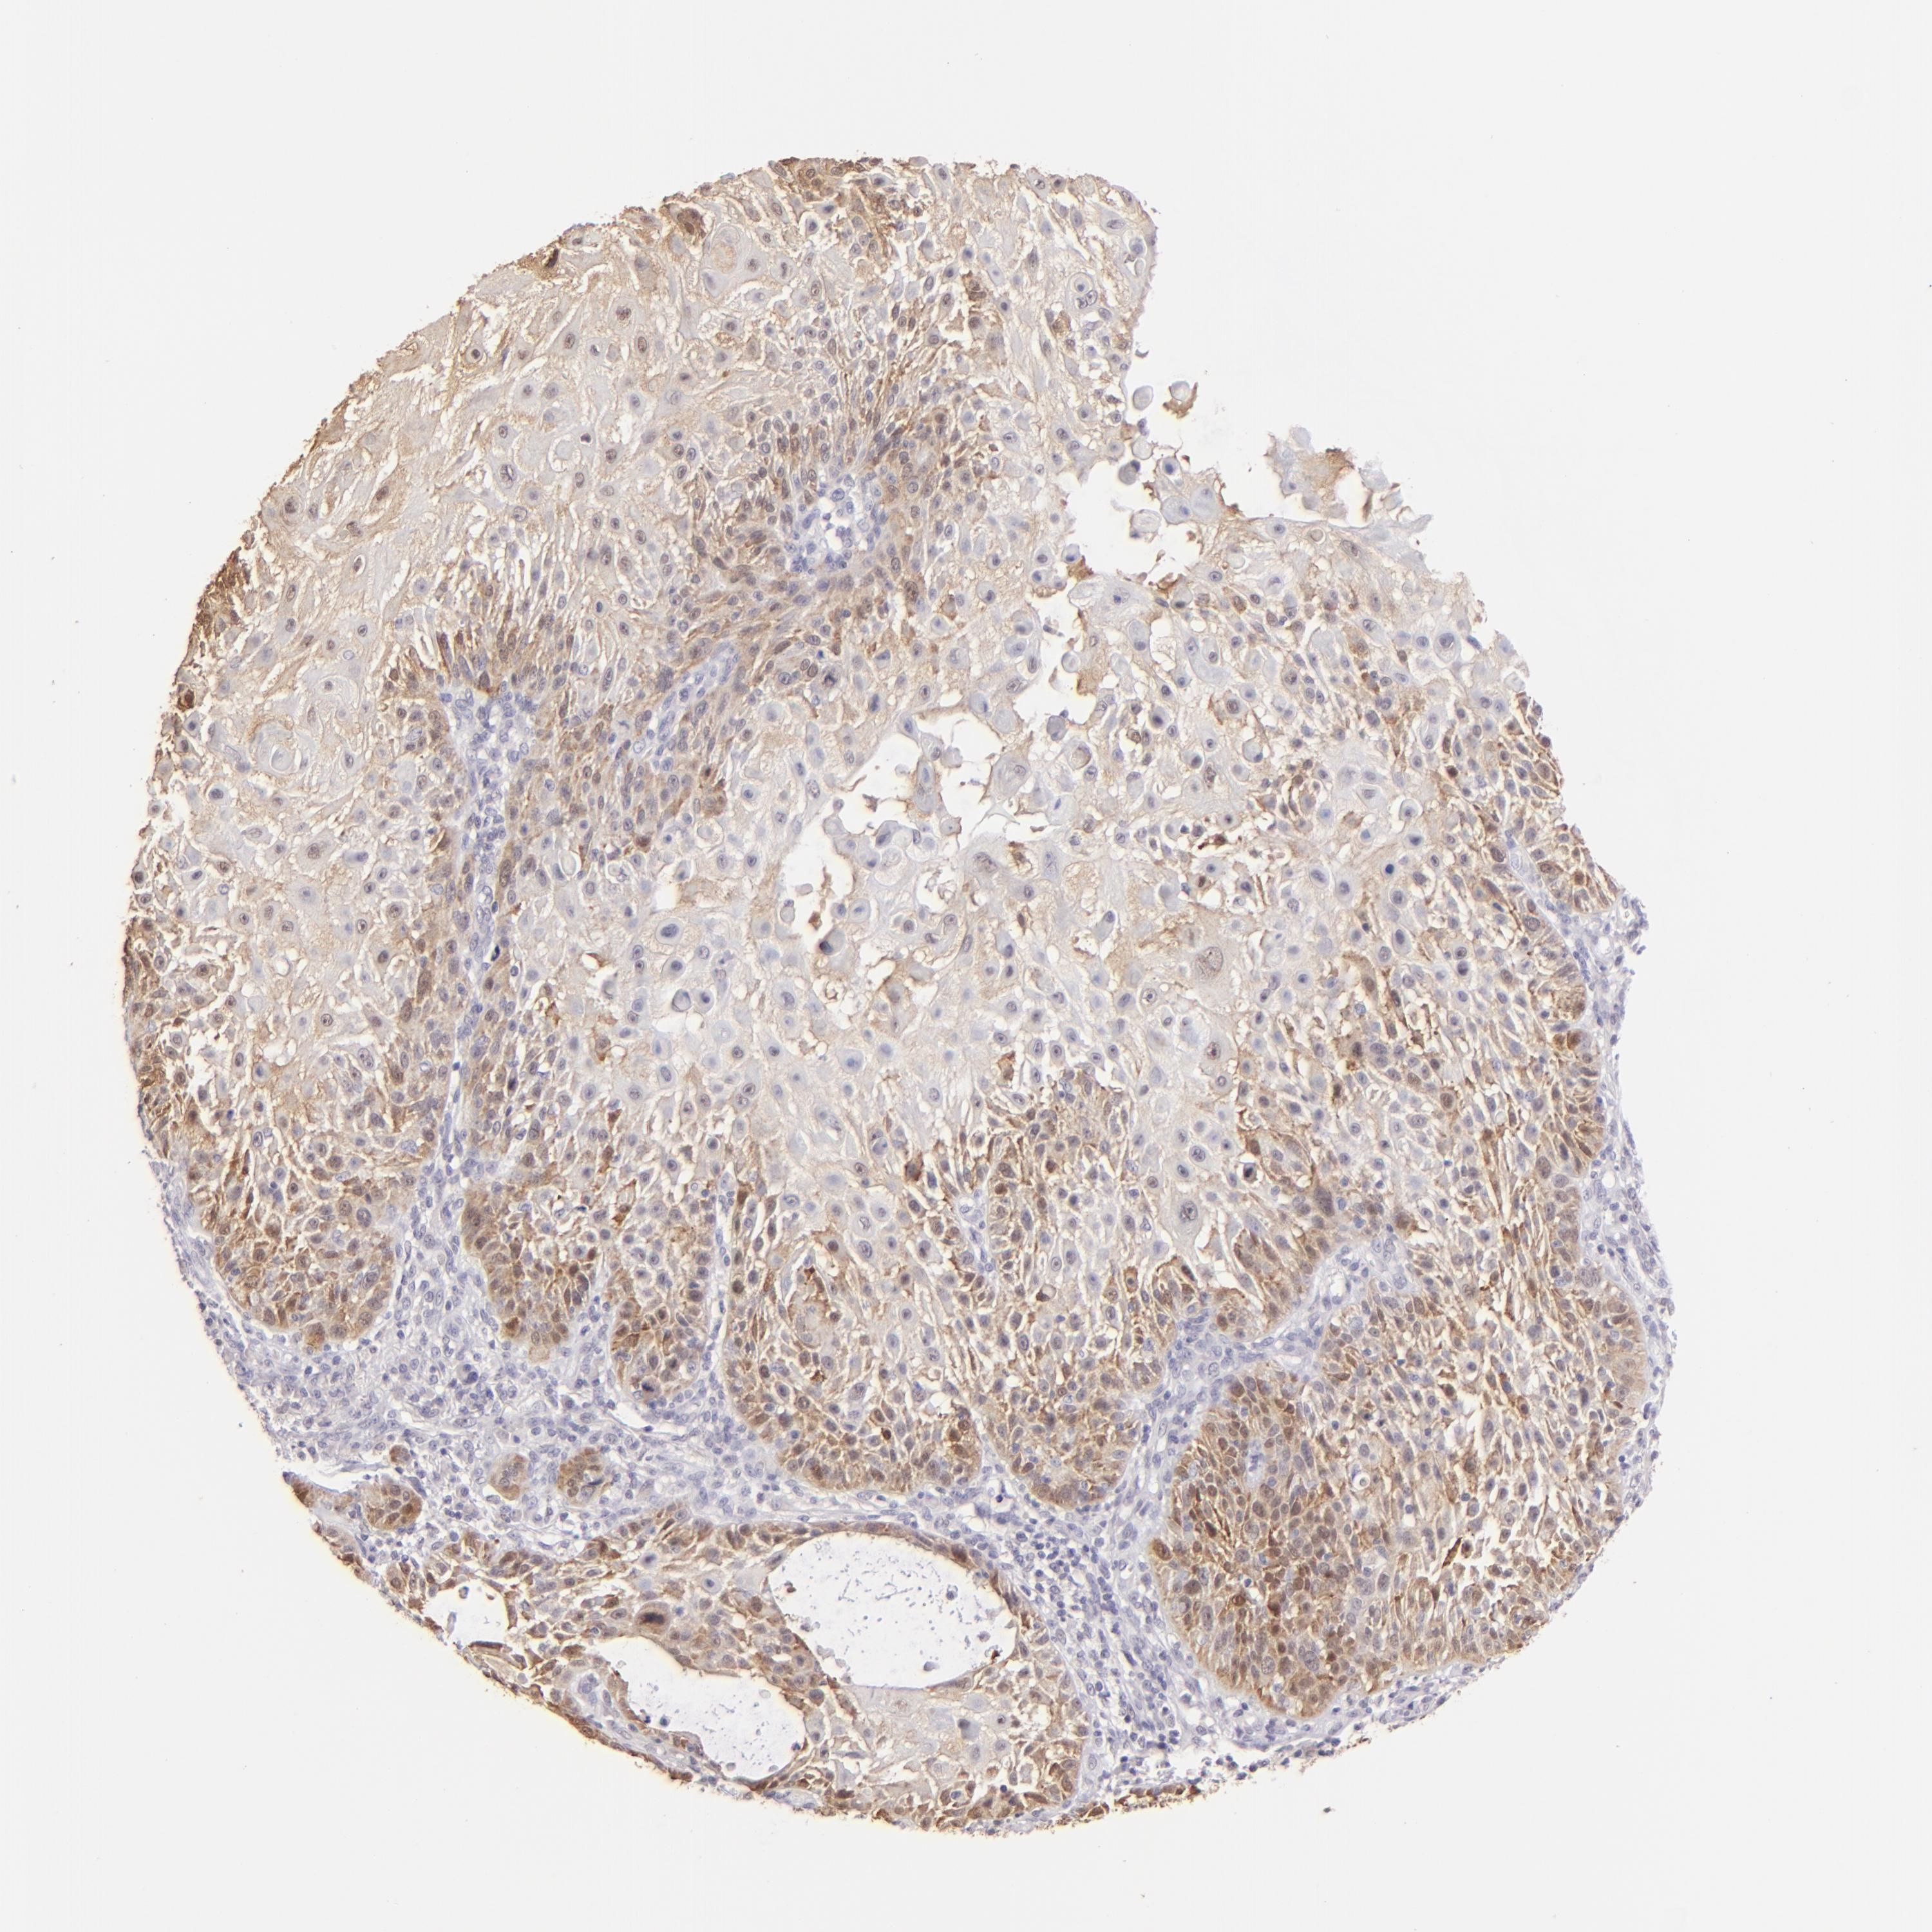

SKIN CANCER - Protein expressioni

A mouse-over function shows sample information and annotation data. Click on an image to view it in a full screen mode. Samples can be filtered based on level of antibody staining by selecting one or several of the following categories: high, medium, low and not detected. The assay and annotation is described here.

Antibody staining in the annotated cell types in the current human tissue is reported as not detected, low, medium, or high, based on conventional immunohistochemistry profiling in selected tissues. This score is based on the combination of the staining intensity and fraction of stained cells.

Each image is clickable and will lead to virtual microscopy that enables deeper exploration of all samples and also displays staining intensity scores, fraction scores and subcellular localization as well as patient and tissue information for each sample.

Antibody CAB002620

Staining

High

Intensity

Strong

Moderate

Weak

Negative

Quantity

>75%

75%-25%

<25%

None

Location

Nuclear

Cytoplasmic/membranous

Cytoplasmic/membranous,nuclear

Squamous cell carcinoma, NOS

Basal cell carcinoma